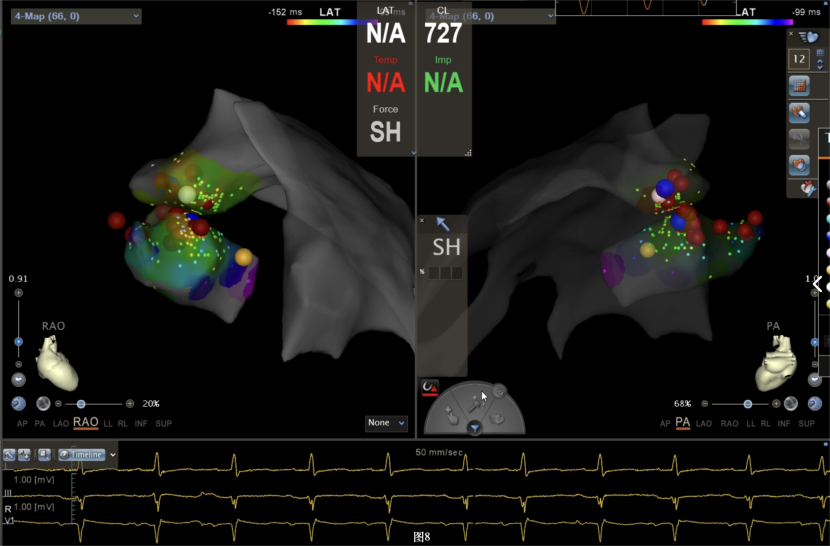

手术中,周明礼团队凭借其丰富的临床经验和精湛的技术,穿刺右股动脉后,将消融大头顺利送入主动脉,于主动脉瓣上标测到最早点(图3红色点)领先体表8ms,电位不理想,果断去到主动脉瓣下左室穹顶部标测,标测到最早点(图4白色点)领先体表25ms,放电消融3s,早搏消失,消融90s后观察2min后,早搏恢复,在该有效点周边补充消融,早搏依旧未能消失,考虑起源点较深,内膜消融未能透壁损伤到起源,随

即穿刺股静脉,将消融大头送至冠状窦内,在GCV远端对应位置标测到最早点(图5绿色点)领先体表27ms,消融后早搏未能消失,周明礼评估起源点偏心外膜,能量依旧不能穿透损伤到起源点,内膜消融基本无效后,果断选择难度系数最为复杂的干性心包穿刺心外膜消融。在导丝的指引下,将消融大头送至心包层(图6),于外膜标测到靶点(图7黄色点)电位领先体表31ms,单极电位无r波且有顿挫,ssummit外膜离冠状动脉较近,比较危险,保证安全,进行了冠脉造影(图7),显示距离LAD和LCx有一定距离,相对安全,随即放电,2s室早消失,10s患者出现心率变慢,该区域走形迷走神经节,消融导致心率减慢,随后保证心率正常的情况下,消融够60s,随后观察半小时,早搏没有恢复,手术成功(图8)。经过不懈的努力,患者恢复了窦率,心脏功能也逐渐恢复正常,手术取得了圆满成功。